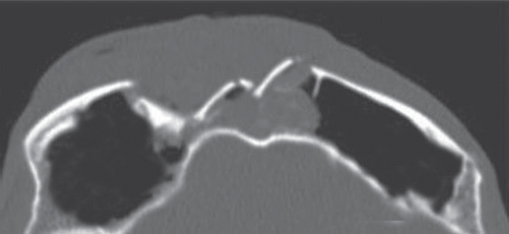

Historically, plain sinus X-rays were used to evaluate facial fractures. Thin cut (1–1.5 mm) axial computed tomography (CT) scans are now the gold standard for diagnosis of frontal sinus fractures. These images are readily reformatted into coronal, sagittal, and threedimensional (3D) reconstructions to improve the diagnostic accuracy. Axial cuts provide excellent information about the anterior and posterior table as well as pneumocephalus ( Fig. 63.5 ). Coronal reconstructions demonstrate the frontal sinus floor, orbital roof, and frontal recess ( Fig. 63.6 ). Sagittal views can assist with evaluation of frontal recess and skull base injuries ( Fig. 63.7 ). Threedimensional reconstructions can be very helpful in delineating the location of bone fragments and reducing the need for excessive dissection intraoperatively ( Fig. 63.8 ). Access to the PACS ( p icture a rchiving and c ommunication s ystem) or some type of presurgical planning software allows the surgeon to manipulate the reconstructions in space, gaining a greater understanding of depth and spatial relationships of the injury ( Video 63.1).